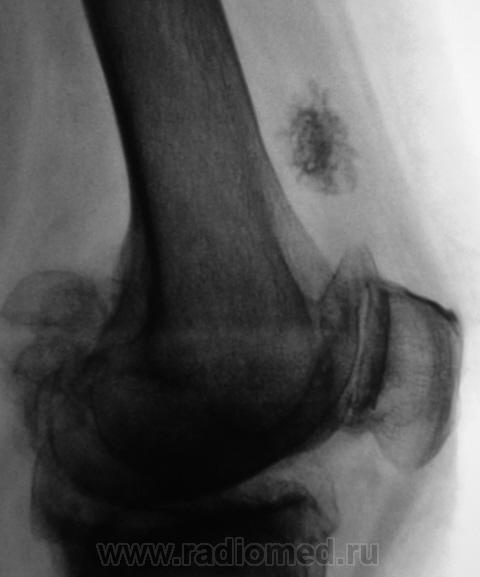

Пациентка направлена на рентгенографию коленного сустава с диагнозом "Деформирующий артроз".

Выраженный деформирующий артроз, множественные хонтроматозные тела в полости сустава.